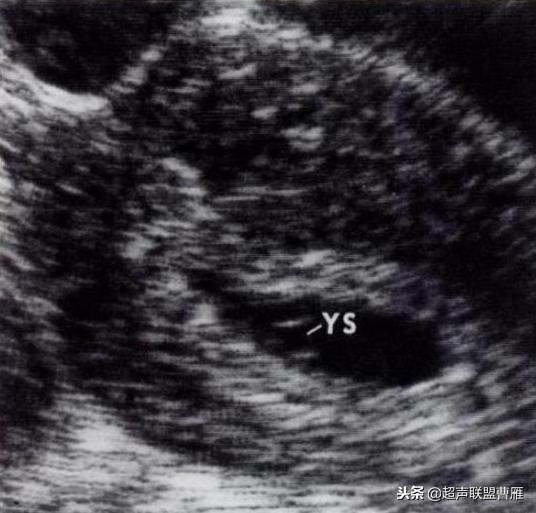

有的图像卵黄囊YS只是两条平行的细短线

妊娠40天,见到卵黄囊、胚极及心管搏动, HCG12800U/L。

卵黄囊高分辨超声图像,妊娠40天